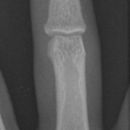

Bennett Fraktur mit geringer Dislokation